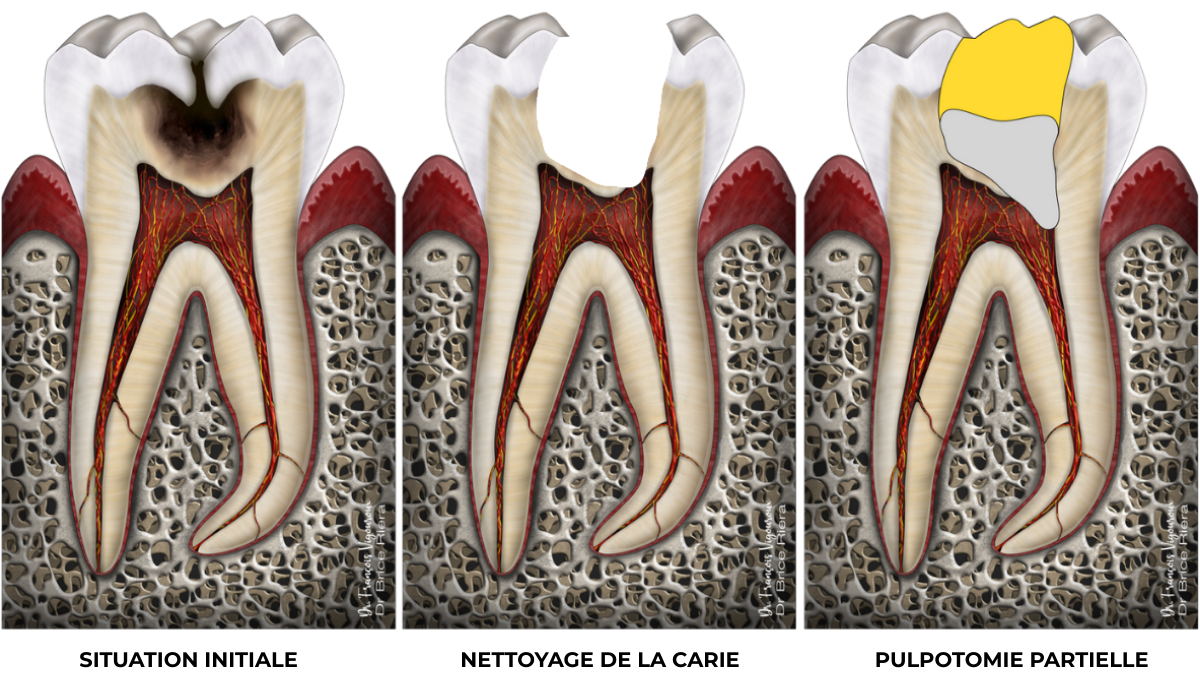

Coiffage pulpaire direct

Si le curetage de la lésion carieuse (schéma du milieu) s’effectue jusqu’à la pulpe dentaire, un biomatériau bioactif (type ciment biocéramique) peut être apposé sur la pulpe exposée.

Schéma de droite : 1 = biomatériau bioactif type ciment biocéramique, 2 = biomatériau de restauration coronaire

Cas clinique

Coiffage pulpaire direct : 90,4% de taux de succès